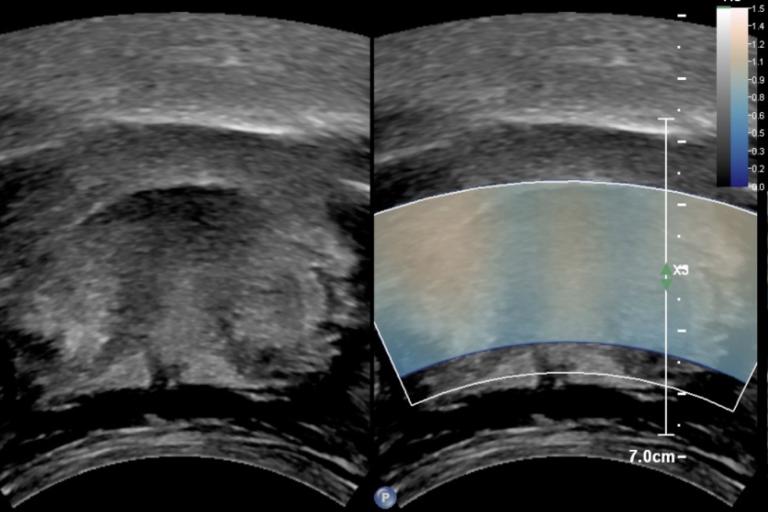

- Liver fat and fibrosis quantification

- Liver fat, inflammation, and fibrosis quantification in non-alcoholic fatty liver disease (NAFLD) and non-alcoholic steatohepatitis (NASH)

- Use of shear wave elastography in novel applications of superficial ultrasound

- Quantitative contrast-enhanced ultrasound for organ and tumor perfusion analysis